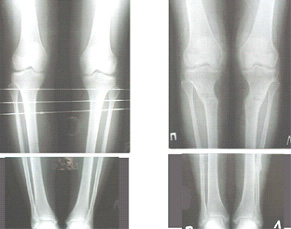

Re: Деформация голеней

Alexander Chelnokov 13 Сентябрь 2005, 23:23

Как уже писал, вчера сделал одну ногу (может, свой плюс будет что не обе- вдвое меньше травма, сразу на костыли встанет, оперированную ножку немного разомнет, тут и вторую заделаем).

Операция была интересной, много полезного опыта приобрел.

Снимки в приложении - фас сравнительный с неоперированной ногой. Жду критики.

Впрос про остеотомию большеберцовой непраздный. Эта получилась при надломе несколько более наклонно, чем я делал (сейчас проблема,

как на второй ноге сделать так же). Вот этот высоящий "зуб" центрального отломка не заменит ли в плане косметики то, что получается при медиализации дистального?

|

Hi Alex:

Nice job!

It is very interesting to me that as you have derotated the tibia you have centred the patella, I think and the prox tibia looks much more anatomic.

The analysis in the attached images is direct, just using the tools.

Tibial tilt is perhaps more than you want but the tibial correction is to 90 (very slight over

correction.

Will need full length views to tell us about the hka but it appears neutral.

Measurements took 4 mins

Derek